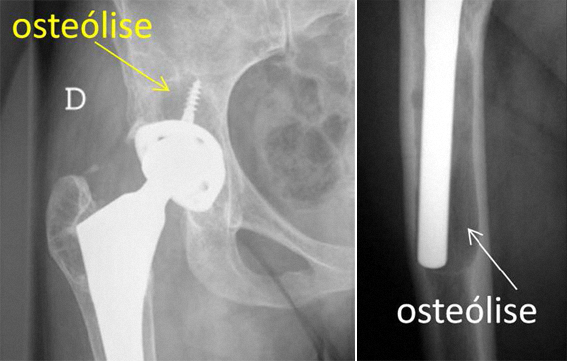

Em casos de osteólise simples e localizada, poderá ser evitada a revisão da prótese colocando enxerto ósseo no local da osteólise.